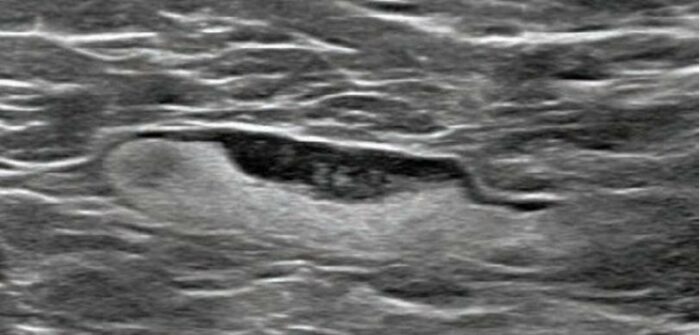

Συμμετοχή μας στό διεθνές σεμινάριο προχωρημένης Ὀγκοπλαστικῆς καί Ἐπανορθωτικῆς Χειρουργικῆς Μαστοῦ ONCOPLASTIA 2025 στήν A Coruña τῆς Ἰσπανίας. Ἀνεπτύχθησαν διεξοδικά νέες τεχνικές, ὅπως ἡ ὑποδόρια τοποθέτηση διατατήρων καί ἐνθεμάτων μαστοῦ, ἡ ὁλοένα αὐξανόμενη χρήση ἐνθεμάτων σιλικόνης μέ κάλυψη πολυουρεθάνης, ἡ διεγχειρητική ἐκτίμηση τῆς βιωσιμότητας κρημνῶν μέ τήν χρήση ἀγγειογραφίας καί ἡ χρήση ἐνδοσκοπικῆς καί ρομποτικῆς…